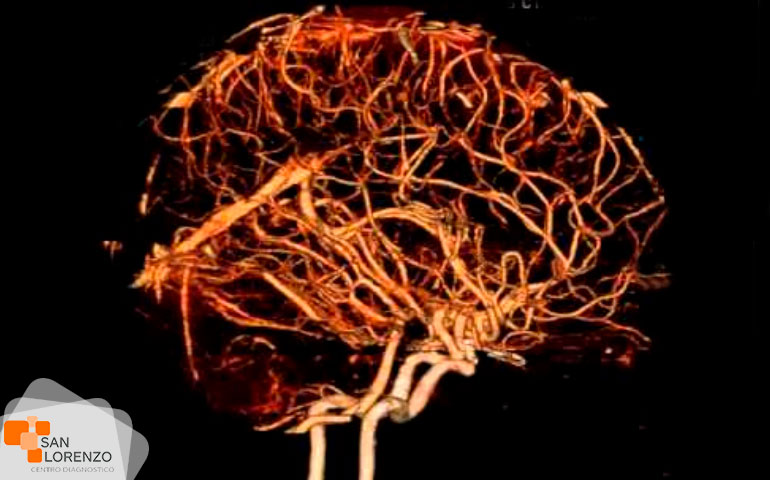

Cuando su médico especialista requiera una mejor visualización de los órganos, o estructuras internas normales o con lesiones, puede solicitar su examen con medio de contraste, éstos son sustancias indispensables para distinguir con mayor claridad áreas del cuerpo o tejidos circundantes que ayuden a diagnosticar condiciones médicas relacionadas con órganos específicos, vasos sanguíneos, o tejidos.

Frente a este requerimiento de su médico, hay que tener en cuenta que los contrastes endovenosos yodados, (usados en las TAC), o los paramagnéticos (usados en las Resonancias), pueden producir alergias o interferir en la función renal en algunos pacientes, como por ejemplo: pacientes monorrenos, con antecedentes de enfermedad renal obstructiva o cuya patología de base pueda implicar compromiso renal secundario; diabetes mellitus, mieloma múltiple, lupus e insuficiencia cardíaca, por lo tanto, en esos casos, todo examen imagenológico que requiera de contraste necesita contar previamente con un examen de creatinina.

Algunos de los exámenes relacionados con medios de contraste son: Angiotac, Urotac, TAC de abdomen y pelvis, TAC de cerebro en lo que se solicite contraste, y todas aquellas Resonancias magnéticas contrastadas.

Todos los exámenes de RM, TAC que requieran contraste tal como los mencionados anteriormente: Angiotac, Urotac, TAC de abdomen y pelvis, TAC de cerebro en lo que se solicite contraste y todas aquellas Resonancias magnéticas contrastadas.